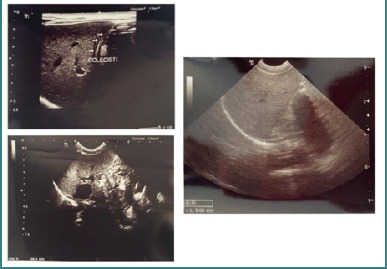

Congenital syphilis is one of the most well-known congenital infections. Despite notable progress in early diagnosis of syphilis paired with the accessibility of cost-effective treatment and preventive strategies, a few cases continue to be diagnosed in the department of obstetrics. This paper presents a case study of an infant with low birth weight, delivered by an adolescent mother, part of a marginalized demographic group. Due to the mother's lack of routine prenatal care, the infant's management required a series of investigations to establish a comprehensive differential diagnosis. Maternal serological assessments for syphilis, including both non-treponemal antibody test (RPR) and treponemal antibody test (TPHA), yielded positive results following fetal extraction via cesarean section, specifically after diagnosis of syphilis in the infant. Within the first 24 hours of life, newborn serologic tests for syphilis (STS) (including RPR and TPHA assays) exhibited reactivity with titers equivalent to maternal samples. Furthermore, at three weeks of life, the neonatal STS titer exceeded that of the maternal titer, displaying a fourfold increase over the maternal STS level. This finding was concomitant with the detection of IgM antibodies against T. pallidum. Screening for other congenital infections yielded negative results. Subsequent to the high-risk infant follow-up, in accordance with the National Guidelines, the infant had a good outcome.